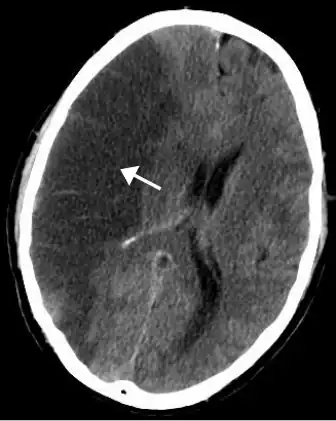

MRI demonstrating white matter changes in the brain of patients with CADASIL

Brain infarct

CADASIL is an inherited disorder caused by mutations in the NOTCH3 gene located on chromosome 19.[19] NOTCH3 codes for a transmembrane protein whose function is not well-known. However, the mutation causes accumulation of this protein within small to medium-sized blood vessels.[19] This disease often presents in early adulthood with migraines, stroke, mood disturbances, and cognitive deterioration. MRI shows white matter changes in the brain and also signs of repeated strokes. The diagnosis can be confirmed by gene testing.[20]